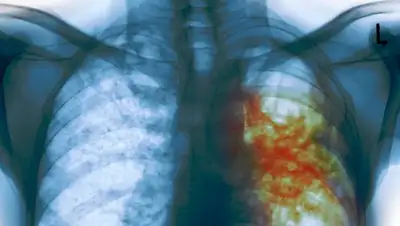

«Самое главное, сегодня мы определили уже перечень лекарственных препаратов на следующий год. Он практически не изменился, но мы добавили туда ряд новых инновационных препаратов для лечения туберкулеза, которые дают эффект при антибиотикоустойчивой форме туберкулеза. Мы долгое время не могли обеспечить ими наших пациентов с такой тяжелой формой заболевания. Получали их от международных организаций в качестве донорской помощи», - сказал он.

По его словам, только каждый пятый пациент с этим заболеванием обеспечивался этим лекарством.

«Этот препарат даже не был зарегистрирован в РК, но благодаря работе с ВОЗ мы достигли соглашения, что эти препараты будут закуплены прямым закупом через ВОЗ. Это позволит 100% больных с лекарственно устойчивой формой туберкулеза обеспечить препаратом», - пояснил глава ведомства.